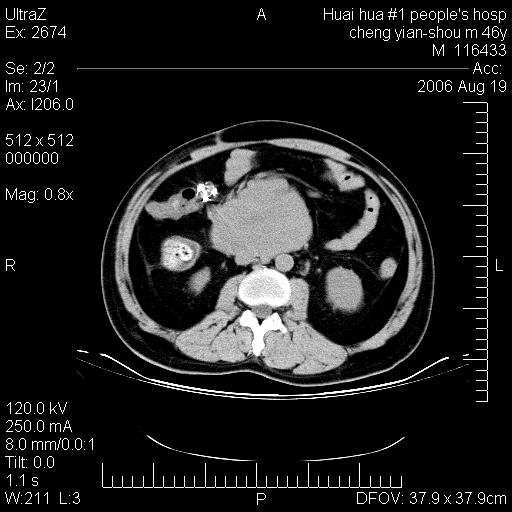

患者,男,46y。腹痛2月,消瘦。

十二指肠水平段占位,考虑间质瘤或平滑肌瘤。

肿块较大,腹膜后占位,境界欠清,周边脂肪密度较高呈条状影,有没有脂肪肉瘤可能,

缺少完整的三期图像。考虑肠系膜脂膜炎mp(肿块型)。

十二指肠水平段占位,考虑间质瘤。

首先考虑小肠间质瘤。

十二指肠水平段软组织密度占位,考虑间质瘤可能性大。

腹膜后占位,境界欠清,考虑来源于十二指肠病变,间质瘤或平滑肌肉瘤可能性大。建议活检。

手术病理结果:原发性小肠恶性淋巴瘤(primary gastrointestinal lymphoma,pgil)是原发于胃肠的淋巴网织系统的恶性肿瘤,在结外淋巴瘤中居第一位,该病少见,临床无特异性,诊断困难,术前主要依靠影像学诊断。胃肠道本身具有较丰富的淋巴组织,因而胃肠原发性淋巴瘤是结外淋巴瘤最常见的部位,文献报道约占胃肠道恶性肿瘤的1%~4%,其中胃约占50%~70%,小肠约占35%~70%,结肠约占4%~6%。影像检查在pgil的诊断及分期中有重要的作用,ct是很有价值的检查方法。

胃肠淋巴瘤病理特点:胃肠道原发性淋巴瘤起源于胃肠壁固有层和黏膜下层的淋巴组织即胃肠粘膜相关淋巴组织(malt),多为粘膜相关淋巴瘤。病理上通常为非霍奇金淋巴瘤,且决大多数来源于b淋巴细胞,很少见于霍奇金淋巴瘤。胃肠原发淋巴瘤比胃肠道癌的发病率要低的多,最常见于胃,其病因可能跟幽门螺杆菌感染有关。幽门螺杆菌能引起胃粘膜损害,引起炎性及免疫反应,淋巴细胞聚集并形成滤泡,可影响胃的正常生理功能,导致胃淋巴瘤的发生。单纯性小肠淋巴瘤是常见好发于回盲末端,受累的肠段较长,可单发、多发,甚至累及整个小肠。原发性大肠淋巴瘤罕见,以直肠和盲肠最多见。病变大体观可表现为胃肠腔内外的肿块,也可表现为从黏膜下到浆膜面肠壁的纵向浸润,并且常常伴有肠系膜淋巴结肿大。任何情况下,肿瘤几乎总是导致一定程度的肠壁增厚,可对称或不对称,病变与正常组织间常无明确分界,肠腔可狭窄、正常或动脉瘤样扩张,后者主要是肿瘤在肠壁内浸润,破坏肠壁内植物神经丛所致。以上改变成为ct检测病变的病理基础。

肠道淋巴瘤的ct表现分为4类

1) 壁内浸润型, (2)多发结节型, (3)肠系膜受累伴腔外肿块型(本型就是),(4)肿块型。